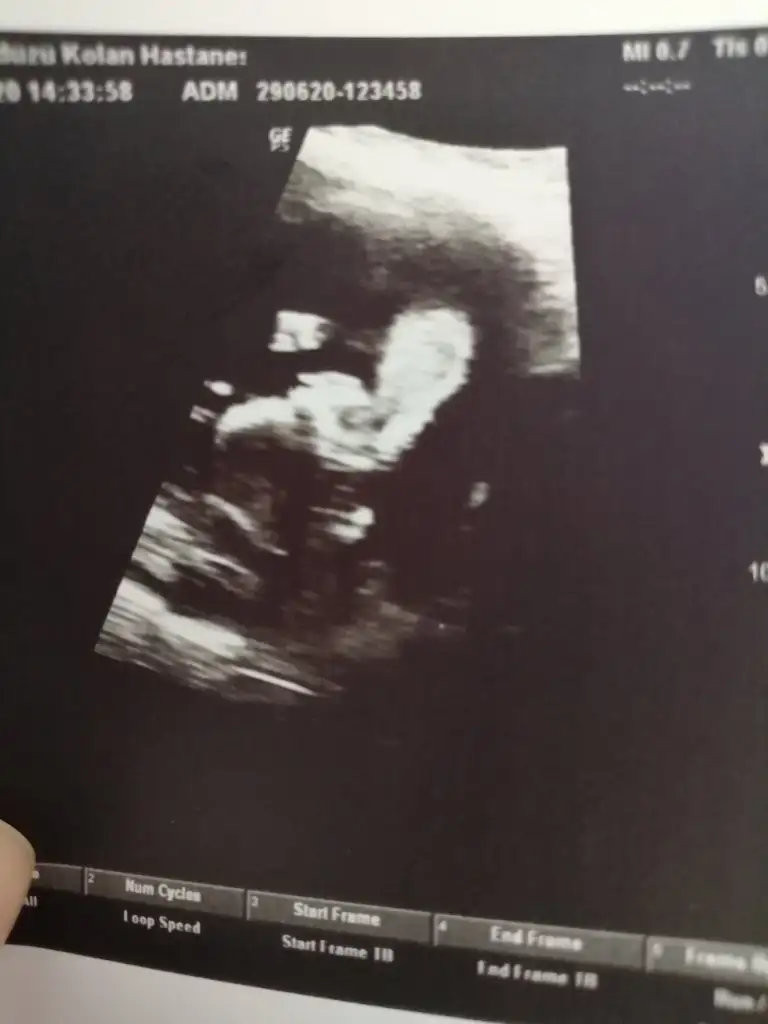

I ikra -meyra bende yorumunuzu merak ediyorum 10 haftalik tam

Eklentiler

• 1593428018684230887551.webp

Merhabalar herkese sağlıklı doğumlar ve bebişler dilerim. benim bebeğim için de bir tahmininiz var mıdır? :)

• IMG_20200630_142810.webp